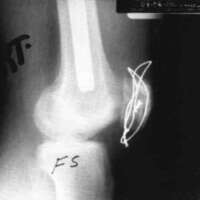

A twenty-nine year old male sustained a high caliber gunshot wound to the left knee (Fig. 4), traversing the lateral femoral condyle through the joint space and through the lateral tibial plateau. Open reduction internal fixation (ORIF) and ligamentous repairs were made. Postoperatively, the patient was placed in a standard cast brace due to the inability to provide adequate medial-lateral stability of the knee surgically (Fig. 5). The cast brace was attached to a continuous passive motion dynamic suspension system to restore and maintain motion (Fig. 6). At the time of the initial cast bracing, the patient had considerable soft tissue edema about the knee. The use of passive motion quickly reduced that swelling to the point where the cast brace provided little support. After one week, the cast brace was reapplied with the addition of a varus producing strap (Fig. 7) and the patient began ambulation training and was discharged. (If atrophy or swelling should continue, the varus producing strap can be easily adjusted to maintain force on the knee and another cast change would not be required).

Figure 5:

Figure 6: